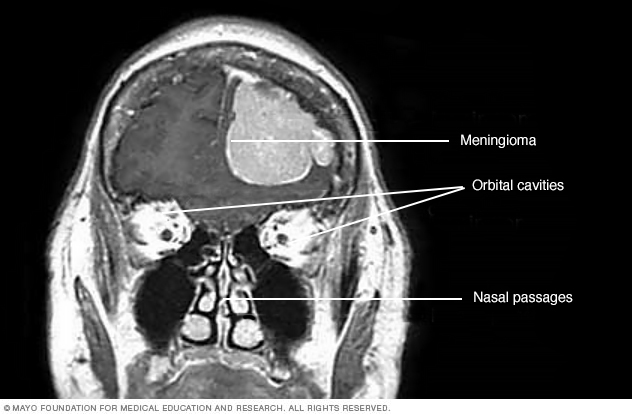

- Meningiomas. Meningiomas are brain tumors that start in the membranes around the brain and spinal cord. Meningiomas are usually benign, but sometimes they can be malignant. Meningiomas are the most common type of benign brain tumor.

MRI scan of a person's head shows a meningioma. This meningioma has grown large enough to push down into the brain tissue." />Treatment

Treatment for a brain tumor depends on whether the tumor is a brain cancer or if it's not cancerous, also called a benign brain tumor. Treatment options also depend on the type, size, grade and location of the brain tumor. Options might include surgery, radiation therapy, radiosurgery, chemotherapy and targeted therapy. When considering your treatment options, your health care team also considers your overall health and your preferences.

Treatment might not be needed right away. You might not need treatment right away if your brain tumor is small, isn't cancerous and doesn't cause symptoms. Small, benign brain tumors might not grow or might grow so slowly that they won't ever cause problems. You might have brain MRI scans a few times a year to check for brain tumor growth. If the brain tumor grows more quickly than expected or if you develop symptoms, you might need treatment.